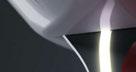

Figura 20. Caso clínico tratado mediante injerto óseo de lámina autóloga. A) Situación clínica basal de la atrofia del segundo cuadrante. Vista lateral. B) Situación clínica basal de la atrofia del segundo cuadrante. Vista oclusal. C) Situación clínica basal de la atrofia del segundo cuadrante. Vista vestibular.

Figura 21. Caso clínico tratado mediante injerto óseo de lámina autóloga. Continuación. A) Obtención del injerto óseo autólogo de la rama mandibular. B) Lámina de injerto óseo autólogo. C) Posicionamiento de la lámina oclusal en la dirección que será fijada bajo el colgajo tunelizado. D) Fijación de las láminas oclusal y vestibular a través del diseño de colgajo tunelizado.

Figura 22. Caso clínico tratado mediante injerto óseo de lámina autóloga. Continuación. A) Reconstrucción volumétrica del área a intervenir antes del primer procedimiento quirúrgico. B) Reconstrucción volumétrica del área intervenida 4 meses después del primer procedimiento quirúrgico. C) Reconstrucción volumétrica de la zona de la rama mandibular de la que se obtuvo el injerto óseo autólogo, inmediatamente después de su obtención. D) Vista oclusal del área a reconstruir, antes del primer procedimiento quirúrgico. E) Vista oclusal del área reconstruida, 4 meses después del primer procedimiento quirúrgico. F) Vista transversal del área a reconstruir, antes del primer procedimiento quirúrgico. G) Vista transversal del área reconstruida, 4 meses después del primer procedimiento quirúrgico. H) Vista transversal de la zona de obtención del injerto óseo autólogo.

Figura 23. Caso clínico tratado mediante injerto óseo de lámina autóloga. Continuación. A) Segundo procedimiento quirúrgico 4 meses después del primero. Situación clínica, vista oclusal. B) Elevación de un colgajo a espesor total con incisión crestal. C) Colocación de implantes en posición de 24 y 26. D) Sutura, cierre primario y cicatrización sumergida de los implantes.

Figura 24. Caso clínico tratado mediante injerto óseo de lámina autóloga. Continuación. A) Tercer procedimiento quirúrgico 3 meses después del segundo. Situación clínica, vista oclusal. B) Segunda fase de los implantes y colgajo a espesor parcial. C) Utilización de matriz colágena xenogénica (MucoGraft, Geistlich®) suturada en vestibular de los implantes para incrementar la cantidad de mucosa queratinizada periimplantaria y profundidad de vestíbulo. D) Cicatrización 2 meses después del tercer procedimiento quirúrgico.